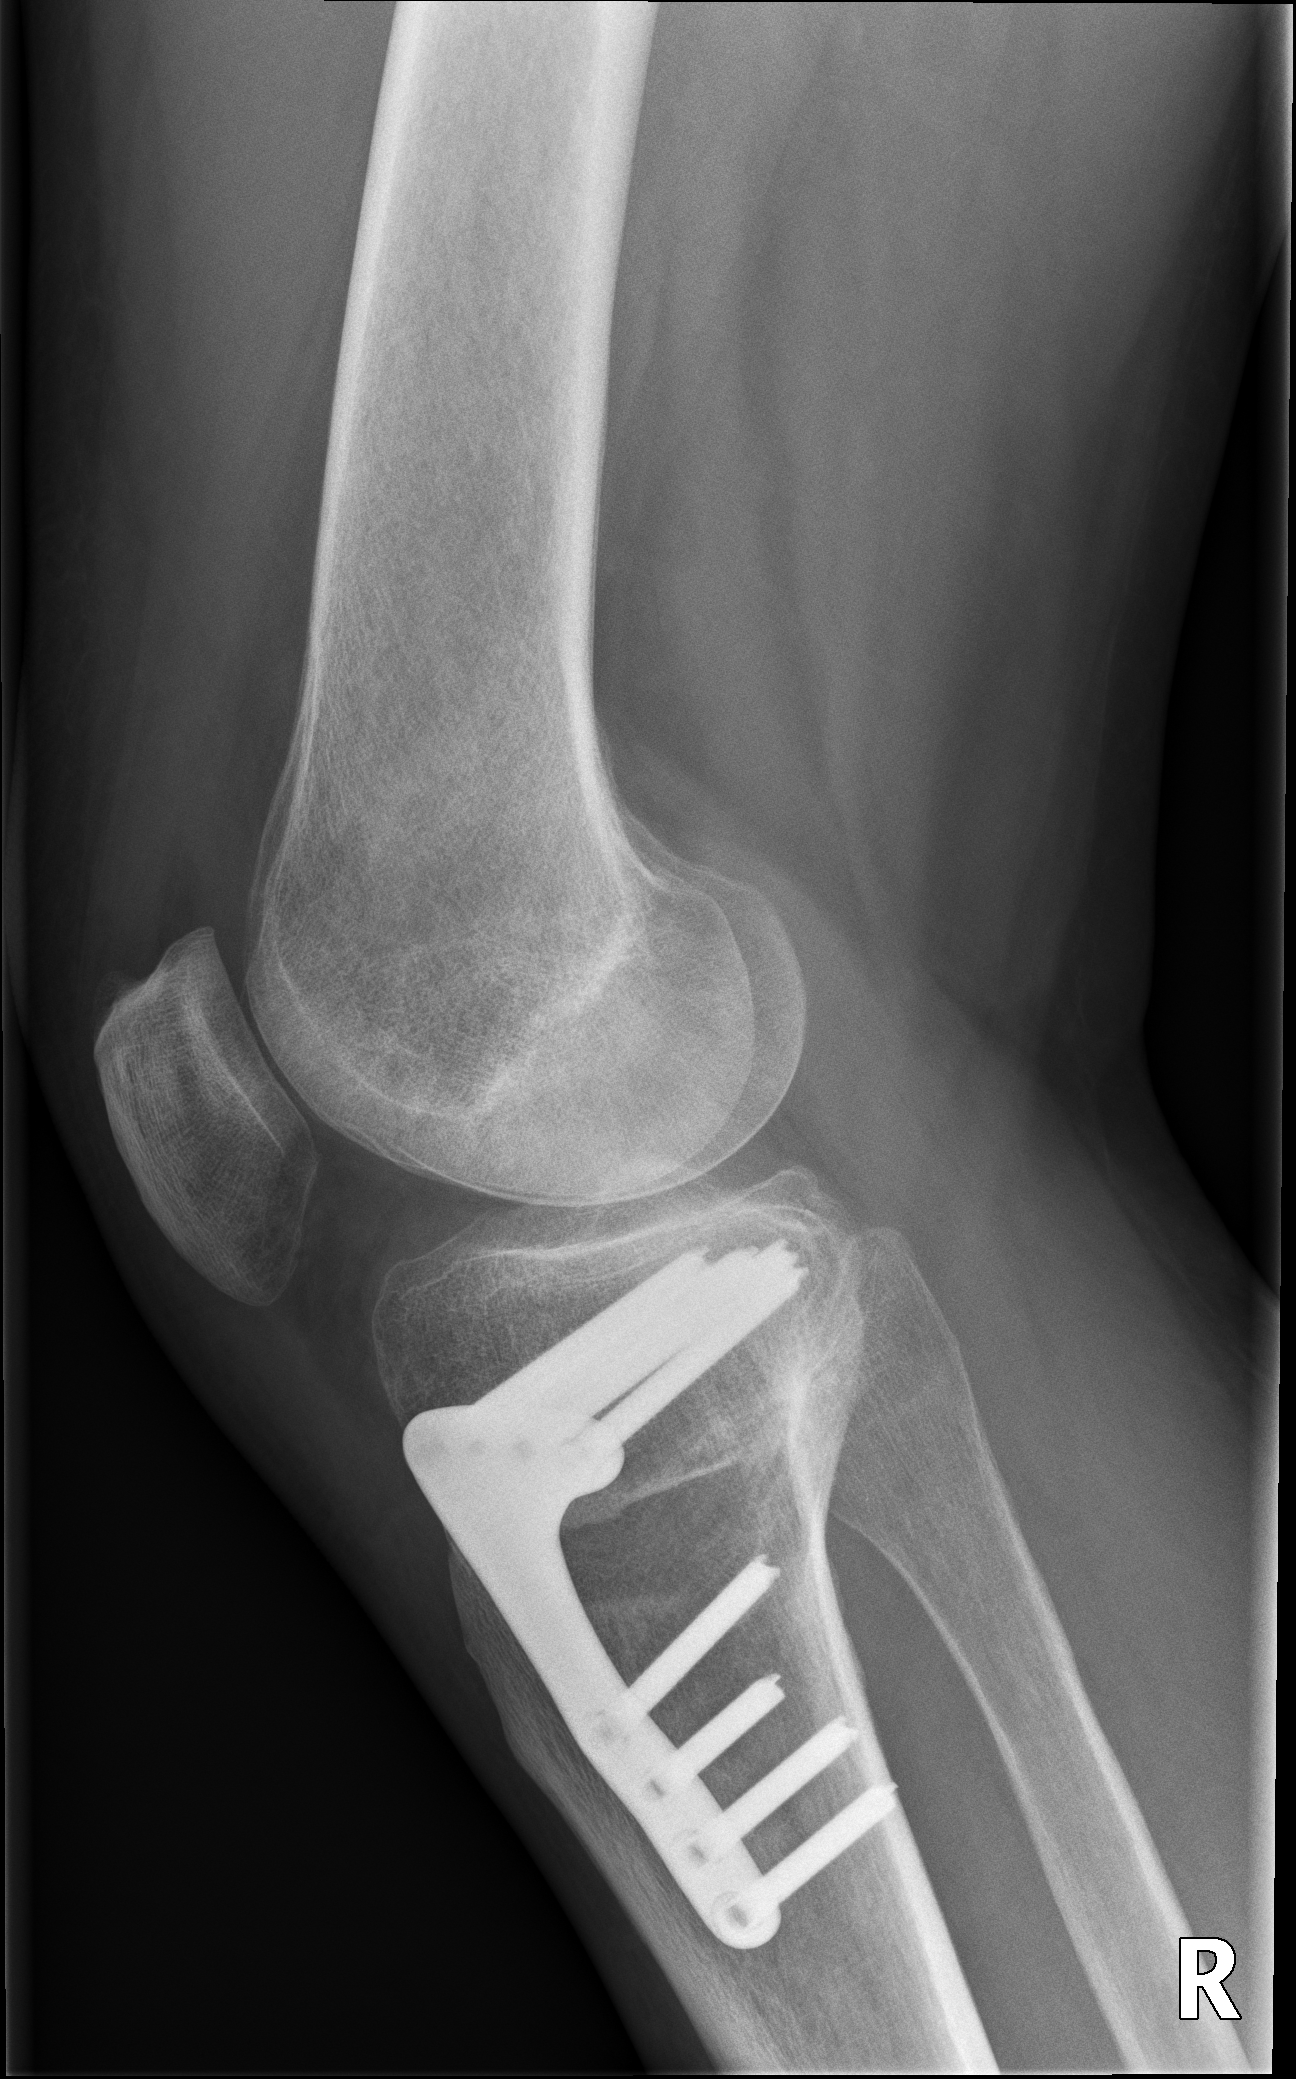

Umstellungsosteotomie

Bei einer Knieumstellung wird eine vorbestehende Fehlstellung des Kniegelenks (O-Bein, oder X-Bein) so korrigiert, dass der Knorpelschaden an der Innen- oder der Außenseite des Gelenks entlastet wird.

Bei innenseitigen Knorpelschäden mit Fehlstellung am Schienbein ist eine Hohe tibiale Osteotomie (HTO, high tibial osteotomy) sinnvoll. Dabei wird im Bereich des Schienbeinkopfes ein Schnitt durchgeführt und dieser Spalt danach aufgeklappt um die Beinachse zu korrigieren. Die Stellung wird mittels Platte fixiert.

Unten: Knöcherne Heilung des aufgeklappten Spaltes nach 5 Monaten.

Bei Knorpelschäden an der Außenseite und Fehlstellung am Oberschenkelknochen ist eine Distale Femur Osteotomie (DFO, distal femoral osteotomy) sinnvoll. Dabei wird im Bereich des körperfernen Oberschenkelknochens ein Schnitt durchgeführt und ebenso aufgeklappt um die Beinachse zu korrigieren. Die Stellung wird auch mittels Platte fixiert.

Die Nachbehandlung richtet sich nach der Art der Operation und der Knochenqualität. Meist wird für 2-6 Wochen eine Teilbelastung empfohlen, eine Schiene ist nicht notwendig. Eine Physiotherapie ist vor allem nach Beginn der Vollbelastung sinnvoll.